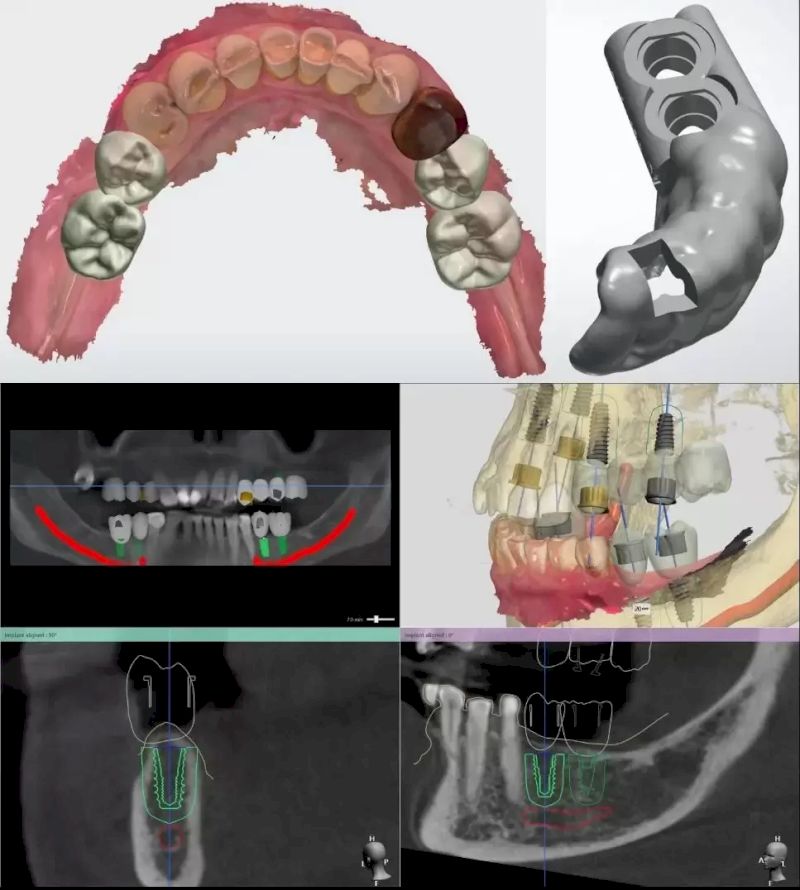

4.3. Lựa chọn công nghệ hiện đại

Ứng dụng những công nghệ tiên tiến vào quá trình cấy ghép Implant giúp quá trình thực hiện diễn ra thuận lợi, nhanh chóng:

Giải pháp trồng răng Implant cá nhân hóa DCT sử dụng máng hướng dẫn phẫu thuật